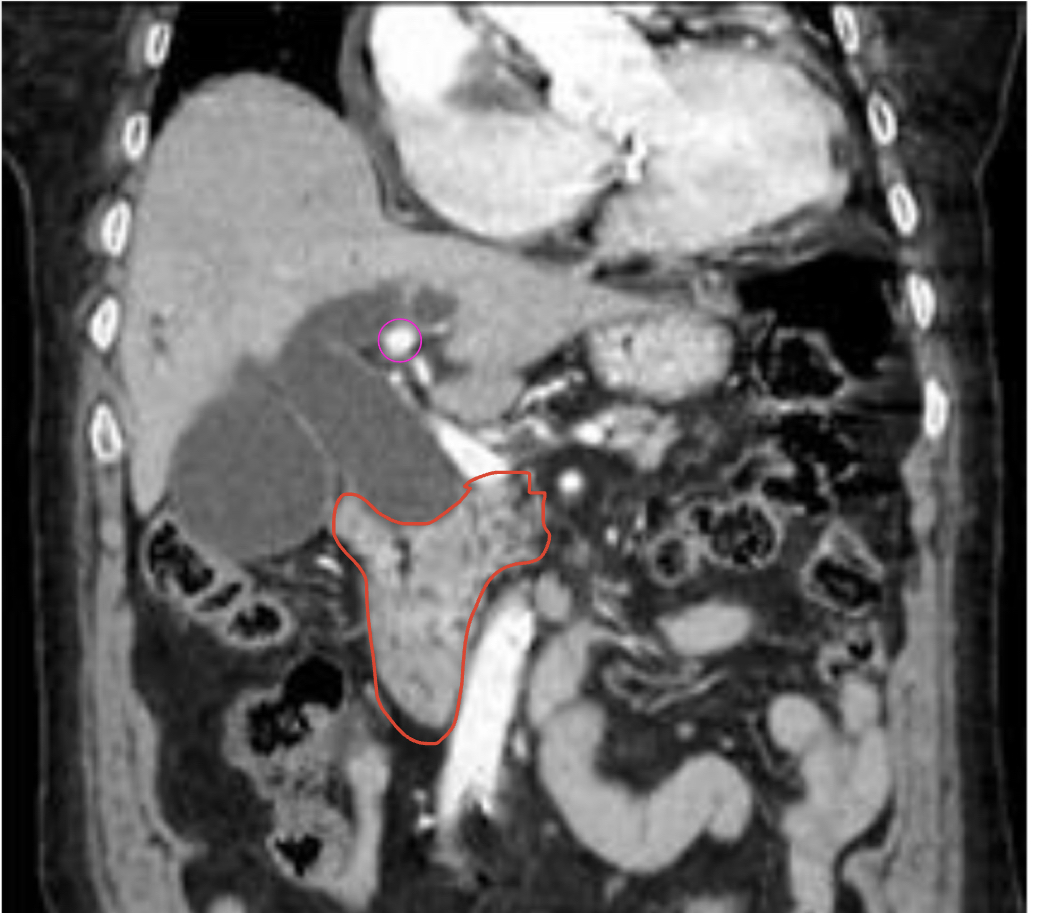

제가 분홍색으로 표시한게 담석이고 빨간색으로 표시한게 이자머리암 맞나요?

빨간색은 periampullary cancer로 관찰됩니다.

보라색은 위치상 담낭, 담관 밖에 있어 담석이 아닐것으로 의심되며 혈관이 잘려보이는것으로 의심됩니다:)